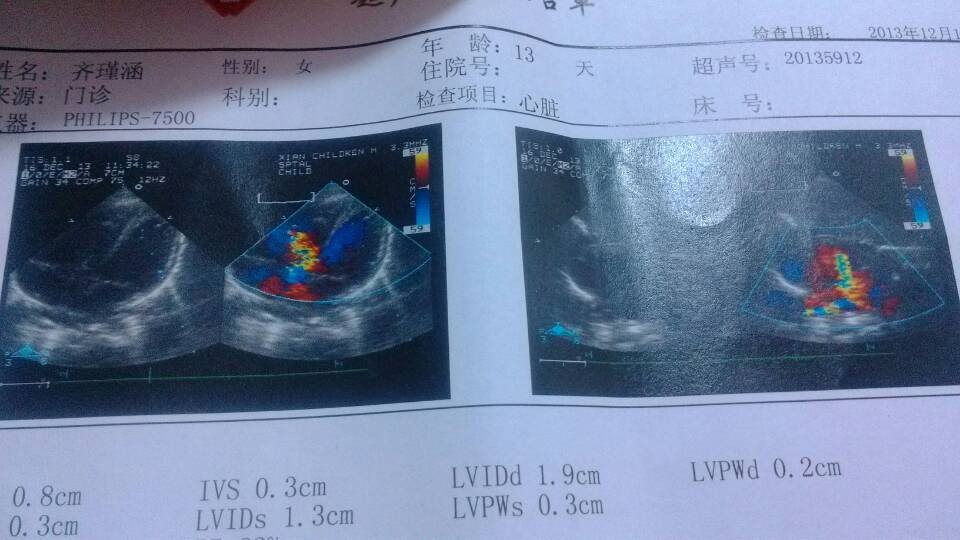

做的B超结果发给您,帮我看看宝宝什么时候能做手术。RVDd:0.8cm IVS:0.3cm LVIDd:1.9cm LVPWd:0.2cm IVSs:0.3cm LVIDs:1.3cm LVPWs:0.3cm FS:31% EF:62% AO:8mm LA:9mm RV:9mm PA:10mm RVOT:13mm LA长/宽:17/13mm RA长/宽:16/15mm LV长/宽:27/18mm RV长/宽:25/19mm 结论是:室间隔缺损(膜周部) 房间隔缺损(中央型)